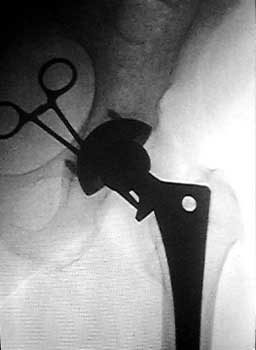

Femoral artery marked. Forceps at area of planned needle

insertion

Sterile prep and drape